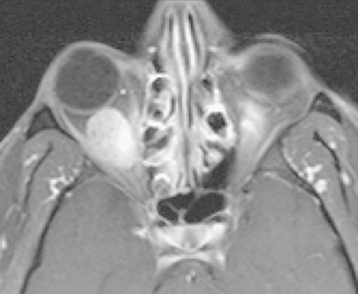

Figure 14.3.2: Axial T1 image with fat suppression and gadolinium of the patient seen in Figure 14.3.1.

Note how both the vitreous and fat are dark, but the extraocular muscles become bright. The orbital mass is now clearly visible. This technique should be performed in all orbital magnetic resonance imagings.